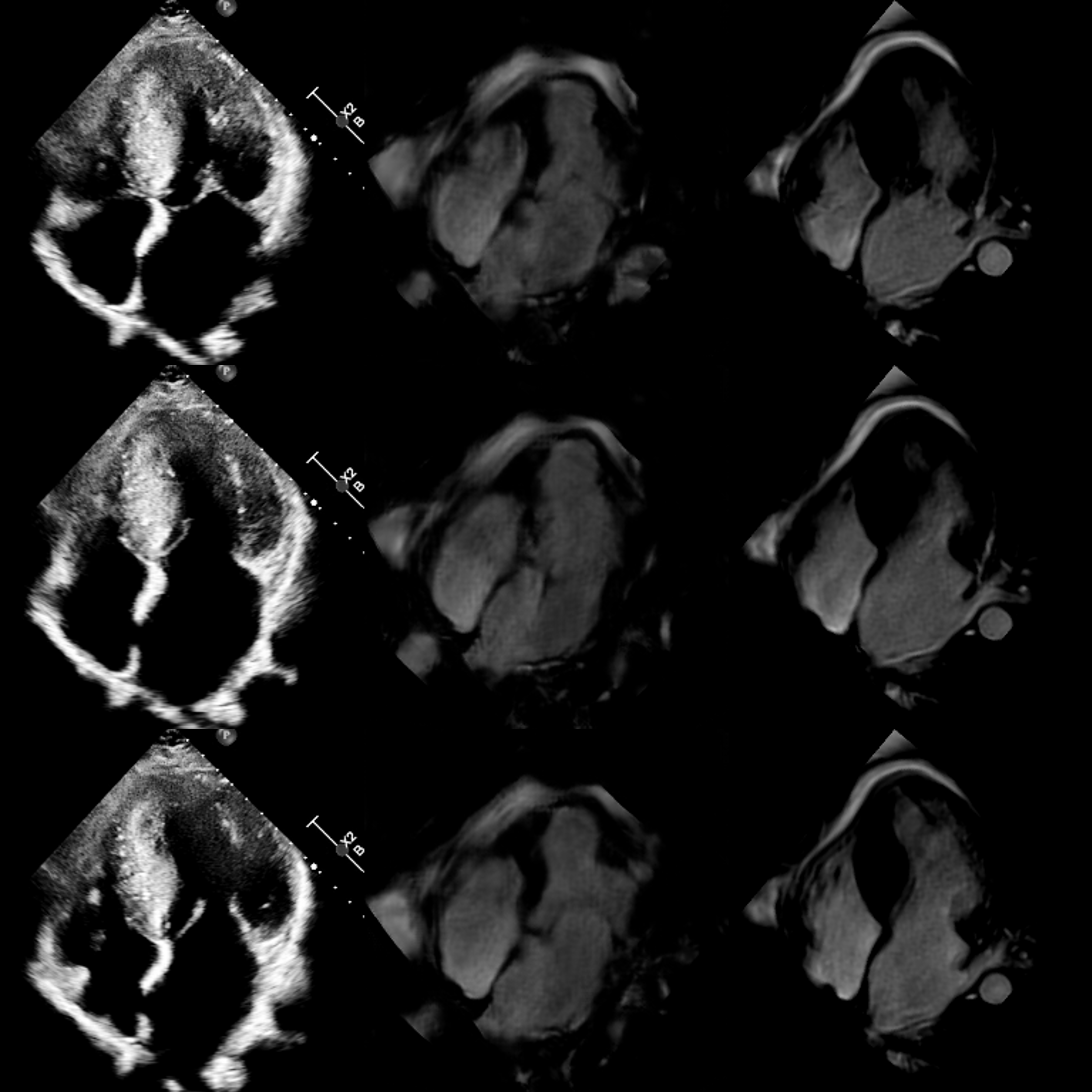

Refer to captionABC

Figure 8: Echocardiography (column A), generated cardiac MRI (column B), and original cardiac MRI (column C) frames across different points of the cardiac cycle for 10thsuperscript10𝑡10^{th}10 start_POSTSUPERSCRIPT italic_t italic_h end_POSTSUPERSCRIPT patient.

To assess the visual quality of the generated cardiac MRI views, we conducted a qualitative evaluation based on several key criteria. Using the test set, we performed echocardiography frame transformation, and compared it with its original echocardiography and time-registered cardiac MRI views as shown in Fig. 8.

Secondly, we check whether the generated views represent the actual cardiac motion throughout the cardiac cycle. This includes ensuring the smooth and consistent transition between systole and diastolic phases and the corresponding movement of the muscles. The consistent transformation of muscle movement’s pace indicates the models can incorporate dynamic information through temporal space. This is especially crucial for RWMA detection to diagnose any onset of myocardial ischemia and infarction (MI).

Finally, we consider the overall visual consistency and quality of the generated cardiac MRI views. This involved checking for artifacts, smoothness, and consistency of the visible arteries and other cardiac features. This is particularly important to validate that the model is not hallucinating while generating the view, but incorporating the information from the source view.

Some typical transformation results over the test set are shown in Fig. 8 along with the source and target views. An extensive set of additional results from the test set are provided in Appendix A111The rest of the results are available in Appendix A. and also in video format online222https://github.com/ilkeadalioglu/Echo2MRI.

Results indicate that the quality of the transformed cardiac MRI views can mostly satisfy the aforementioned criteria and usually present a similar or sometimes even better visual quality than the corresponding actual (target) cardiac MRI views. To validate this claim, we further performed a “Confusion Test” as part of the domain expert evaluation, which will be presented next.